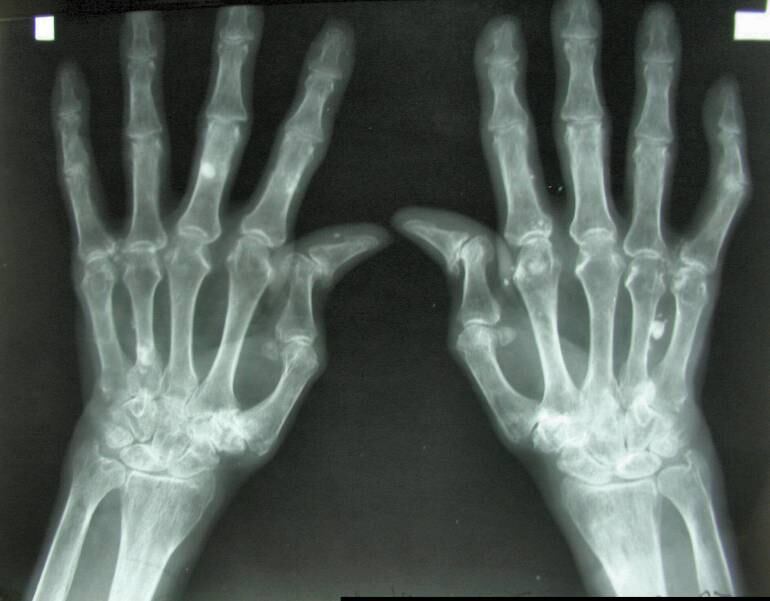

(C.C Google Images )

Esta enfermedad del sistema inmunológico, encargado de proteger y defender al cuerpo de virus y bacterias; afecta en este caso principalmente las articulaciones, más no exclusivamente. Se caracteriza por presentar dolor, inflamación y limitación de las funciones en las articulaciones que deriva en deformidad importante. Afecta tanto manos y pies, con menor frecuencia articulaciones grandes como hombros y cadera.